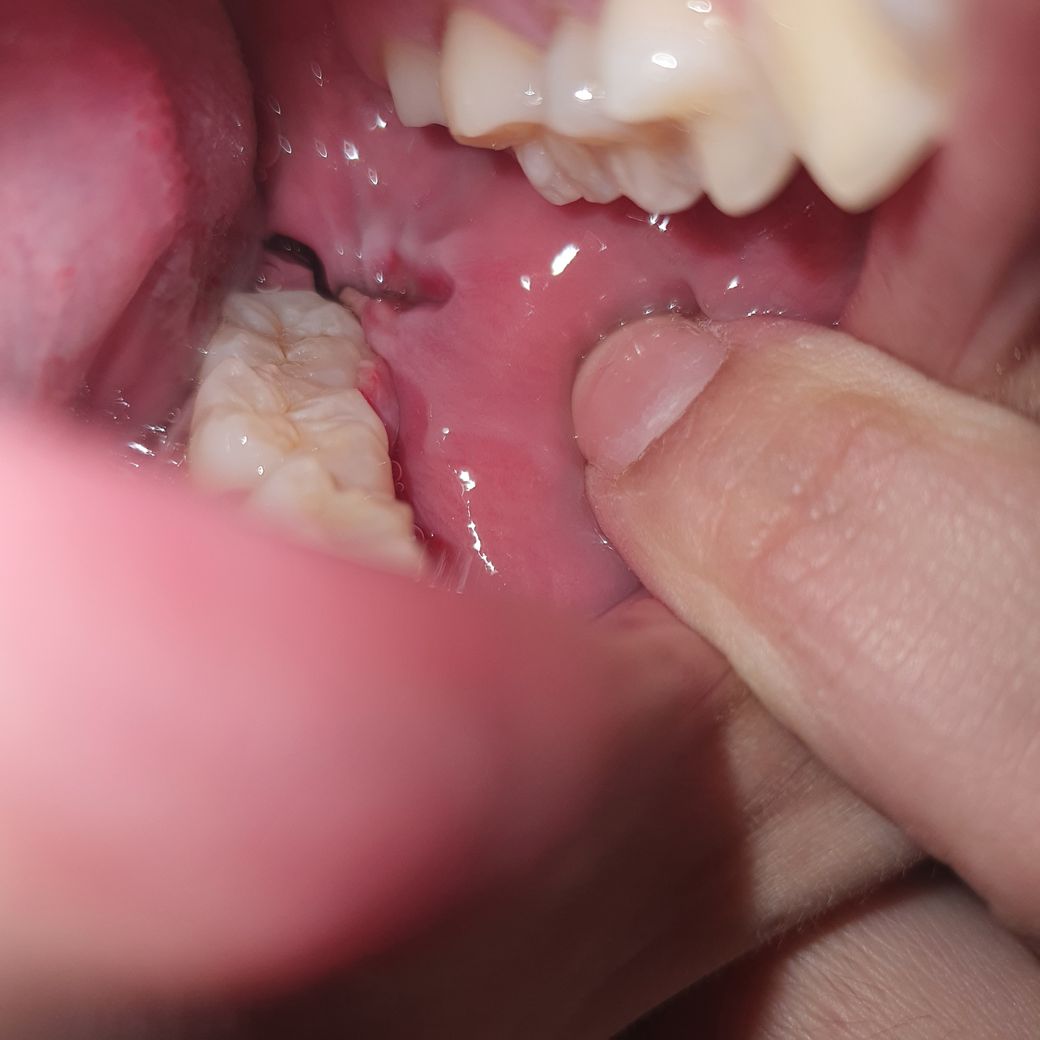

이건 오늘 입니다.. 저거 흰색 이물질일까요? ㅠㅠ

계속 냅두면 볼살 차오를까요? 사진상으론 잘 안보이는데 많이 파였거든요..

흰색은 잇몸이 치유되는 조직으로 보이고

벌어진 부분은 시간이 지나면 살로 채워집니다.

사랑니 발치후 실밥은 잇몸을 메꾸는 목적이 아니라 음식물이 덜 들어가게 하는게 목적입니다. 실밥이 풀어져도 크게 문제가 되지 않습니다.

해당 정도는 시간이 지나면 자연스럽게 붙게 되고 살이 차오릅니다. 구강 내 상피는 다른 조직에 비해 회복력이 크기 때문에 지금 정도로도 크게 문제가 되지 않습니다. 따라서 크게 걱정하지 않으셔도 되고 시간이 지나면 자연스럽게 해당 부위가 아물며 주변 잇몸이나 조직과 같아지므로 걱정하지 않아도 됩니다.